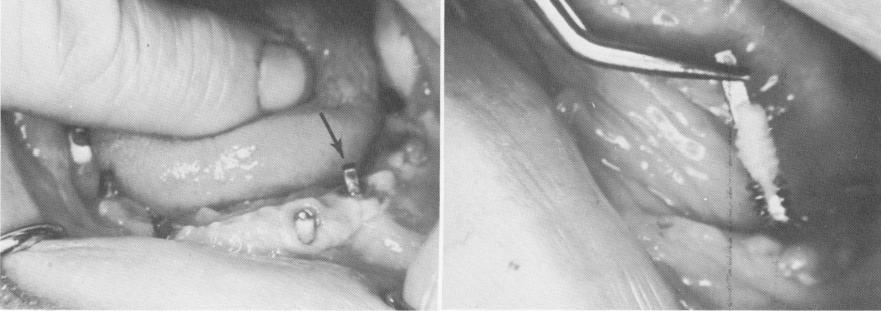

Case 3. A male patient, age 60, received a traumatic injury to his left mandible during a car acci-

dent. One of his vent-plants, which helped support a full arch fixed prosthesis, was knocked loose from the surrounding bone with a good portion of bone attached to it. However, the one directly nearest to the implant was still attached. The bridge and the implant were removed (Fig. 4-53). Since the patient did not appear for at least 6 weeks after the accident, the outer aspect of the bone attached to and surrounding the implant acted as a sequestrum, and therefore the lacunae in this area were devoid of osteocytes. The innermost surface of the bone contained osteocytes in the lacunae, since these cells were nearest

Fig. 4-53. A, The full-arch prosthesis was removed, exposing the vent-plants and the one remaining left cuspid tooth. The arrow points to the loosened implant. B, Bone was firmly attached to the vent-plant.